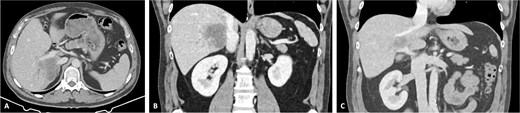

Vascular clamps were applied to the IVC. Before resection, we measured the expected vascular defect. An IVC defect measuring 5 cm in length and 2.5 to 3 cm in width was confirmed. The patch was tailored to 6 × 4 cm, allowing a repair larger than the defect to avoid tension and stenosis. We proceeded with resection of the IVC anterolateral wall. Reconstruction using the APFP, with the mesothelial side of the patch facing the lumen, was performed using a running 4–0 polypropylene suture (Fig. 4). It is essential to flush the vein with heparinized saline and avoid suture tension. Total IVC clamping time was 30 min. The video vignette demonstrates the surgical technique. The specimen is shown in Fig. 5.

Reconstruction of the IVC with APFP. (A) Intrahepatic cholangiocarcinoma infiltrating the IVC; (B) after assessing the area of IVC resection, the APFP is measured and prepared; (C) following vascular clamping, tangential resection of the IVC anterolateral wall is performed; (D) traction sutures are placed at the borders of the APFP and the corners of the IVC; (E) the APFP patch is sutured using a running 4–0 polypropylene suture; and (F) the vascular clamp is removed, and the reconstructed IVC is inspected for bleeding and stenosis.

Final specimen. The resected specimen shows intrahepatic cholangiocarcinoma with invasion of the IVC.